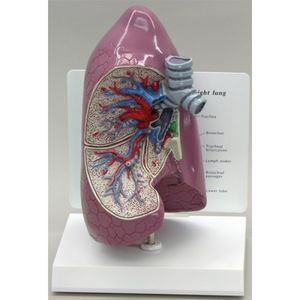

... Modelo a tamaño natural del pulmón derecho, disecado por un lado para mostrar la bifurcación de la tráquea,los bronquios,los vasos sanguíneos y los ganglios linfáticos.En la base, no disecable ...

Educational + Scientific Products Ltd

... Este modelo anatómico de pulmón muestra los bronquios, las arterias, las venas, los ganglios linfáticos, el paso bronquial y la bifurcación de la tráquea. ...